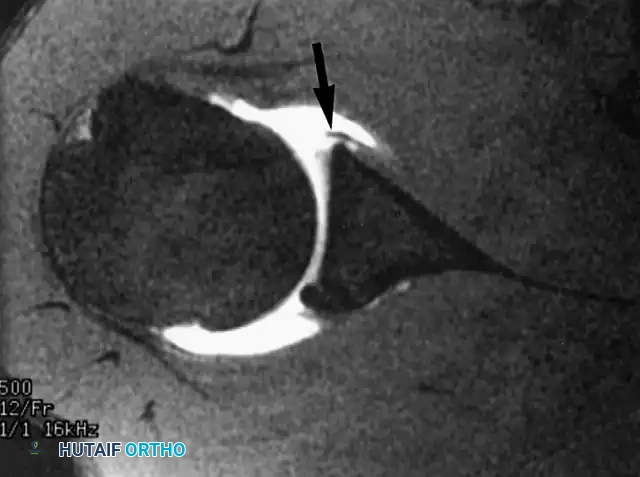

The Shoulder: Labral Pathology and Paralabral Cysts

Although the primary focus of extremity coils often centers on the distal segments, the shoulder joint frequently presents with complex capsulolabral pathologies that require high-resolution MRI arthrography for definitive surgical planning.

Anterior Labral Tears and MRI Arthrography

The glenoid labrum is a critical static stabilizer of the glenohumeral joint, deepening the glenoid concavity by approximately 50% and serving as the attachment site for the glenohumeral ligaments.

Surgical intervention is indicated for recurrent anterior shoulder instability, persistent pain following a traumatic dislocation, or failure of a comprehensive 3- to 6-month conservative rehabilitation program. MRI arthrography is the gold standard for identifying Bankart lesions, anterior labroligamentous periosteal sleeve avulsions (ALPSA), and Perthes lesions.